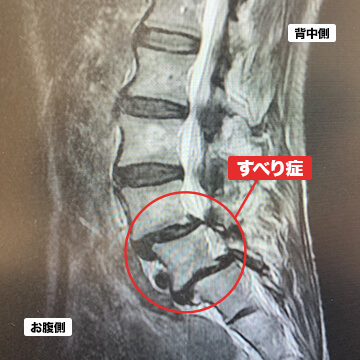

- 腰椎すべり症

腰椎すべり症とは、上下の腰骨が前や後ろに滑ることを言います。腰骨が滑ることで脊柱管狭窄症と同様に神経の圧迫が起こり、腰痛や坐骨神経痛、間欠性跛行の症状が現れます。腰骨は一度すべると元に戻すことはなかなか難しいとされているため、進行を抑えるためにも激しい運動などは控えなければなりません。